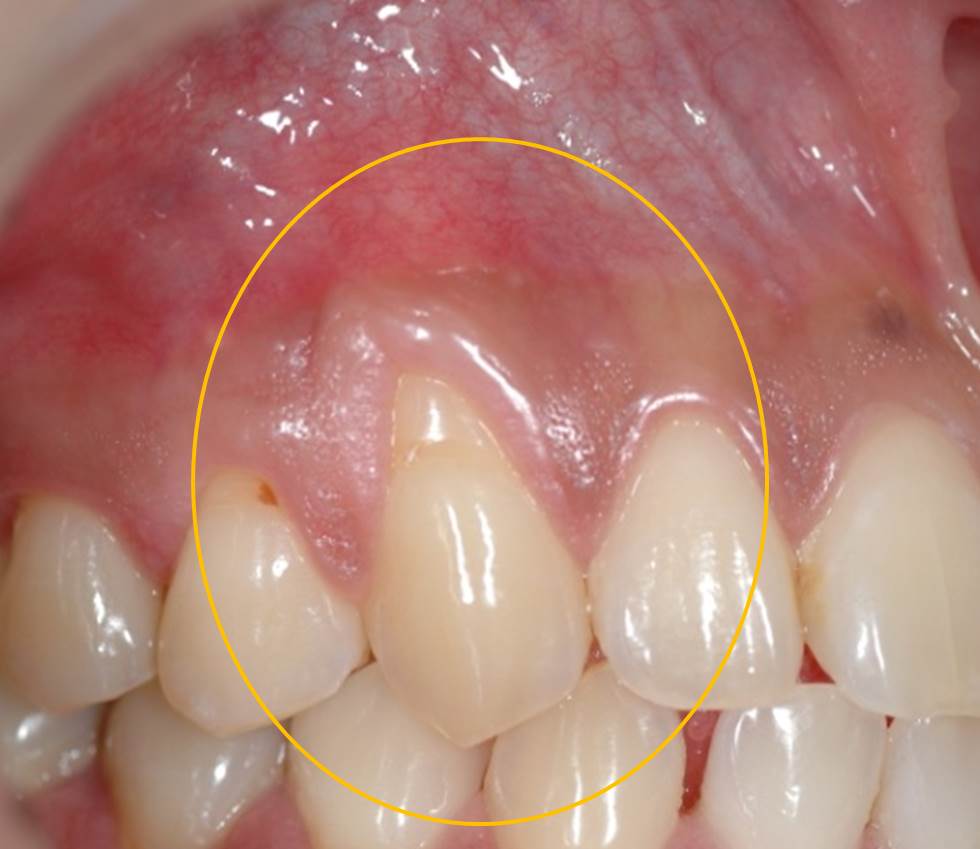

下写真です。オレンジ○部分に歯肉退縮(歯茎の痩せ)が認められます。

ミラーのClass1の症例に対して歯肉結合組織を移植して両側歯間乳頭にてカバーしました。歯肉退縮した歯の両サイドに骨吸収が認められないため根面被覆の成功率は高いことが予想されました。